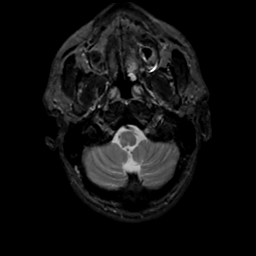

MR Study #8, March 31, 1991 -- Slice #5